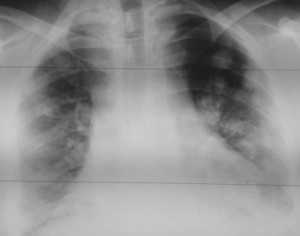

Как выглядят метастазы в легких на рентгене? Слева — узловые образования у пациента с раком яичка. Справа - метастазы рака яичников гематогенного характера с выраженным опухолевым лимфангиитом (обратите внимание на деформированный сетчатый, линейный характер легочного рисунка).

Лимфогенные метастазы легких на КТ выглядят как множественные мелкие диссеминированные очаги. Они расположены вдоль междольковых перегородок и плевры. Картина напоминает туберкулез и саркоидоз, и в этой связи часто требует уточнения. Вместе с лимфогенными метастазами легких почти всегда обнаруживаются патологические изменения (увеличение) лимфатических узлов средостения.

Лимфогенные метастазы на рентгене и КТ выглядят как множественные мелкие очаги с диссеминированным распространением, локализованные в междольковых перегородках, в плевральных листках. Вокруг можно видеть характерную картину ракового лимфангиита. Кроме того, практически всегда выявляются патологически измененные и увеличенные лимфатические узлы средостения. Лимфогенное метастазирование необходимо дифференцировать с милиарным туберкулезом, саркоидозом. Иногда это требует привлечения Второго мнения.

Лимфогенные метастазы проявляются увеличением лимфатических узлов средостения в сочетании с мелкоочаговой диссеминацией с очагами до 2-3 мм в диаметре вблизи плевры и в междольковых перегородках, а также по ходу бронхов и сосудистых пучков.